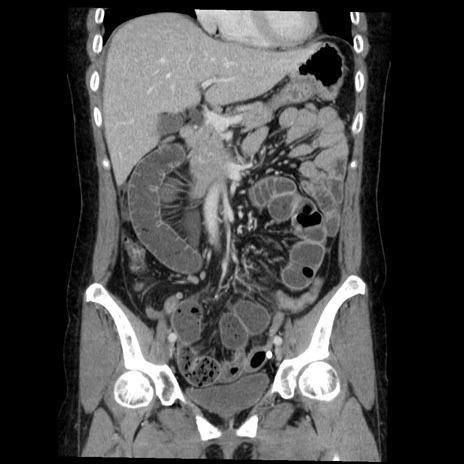

症例6(冠状断像)

【症例】50歳代女性

【主訴】下腹部痛

【現病歴】本日朝より下痢2回あり。 昼食を食べた後、嘔吐3回、下腹部痛認め、症状軽快せず、当院救急搬送。

最終食事:本日昼(生ものなし)。 昨日の夜、刺身を食ぺたとのこと。周囲に同様の症状の者なし。普段、排便は毎日あるとのこと。

【既往歴】卵巣癌術後(8年前に当院で卵巣摘出)

【身体所見】 意識清明、腹部:平坦、腸蠕動音→、やや硬、下腹部自発痛・圧痛あり、反跳痛あり、筋性防御なし。

【データ】WBC 16000、CRP 0.01